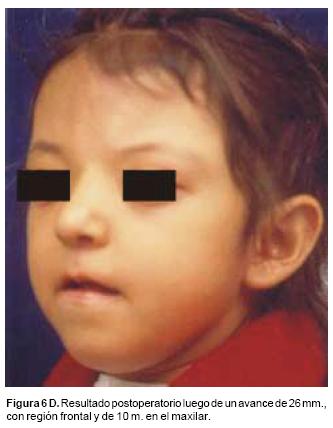

También los controles radiológicos durante el proceso de distracción mostraron que no se produjo la creación de espacios muertos intracraneanos durante los avances. En todos los pacientes con sinostosis bicoronal el avance frontoorbitario produjo excelentes resultados estéticos dando una nueva forma a la región frontal y proyectando mejor el reborde supraorbitario. En los niños con enfermedad de Crouzon y síndrome de Apert, se corrigió en forma muy satisfactoria el exorbitismo al resolver las graves exposiciones corneales (Figuras 5 A, B, C, D, E, F, G, H), en los que se utilizó el avance simultáneo del tercio medio, este cambio óseo corrigió muy satisfactoriamente la retrusión del mismo, ampliando la vía aérea y resolviendo en muchos casos grandes problemas ventilatorios durante el sueño (Figuras 6 A, B, C, D, E, F). Los pacientes con plagiocefalia corrigieron significativamente la deformidad frontoorbitaria y los tejidos blandos suprayacentes se adaptaron a la nueva estructura ósea. La clásica órbita de arlequín de estos niños producida por la sinostosis del frontal con el esfenoides, inmediatamente se ve corregida en su forma y su configuración se hace muy similar con la órbita contralateral (Figura 7)(Fig. 7a, 7b, 7c, 7d, 7e, 7f, 7g) (Cuadro II).